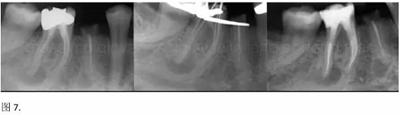

開髓后預(yù)敞、探查根管、建立直線通路是根管機械預(yù)備的第一步。在這些階段中,醫(yī)生可能會經(jīng)常遇到一些困難。這些難題包括器械折斷、臺階形成、根管歧坡或根管拉直、帶狀穿孔、根尖穿孔、根尖肘形、根尖堵塞。所有這些錯誤可導(dǎo)致根管系統(tǒng)清潔不完善從而降低牙髓治療成功率。

本文的目的是描述一種旨在優(yōu)化根管根尖部分預(yù)備的預(yù)敞技術(shù)。根管頸部或冠方的早期預(yù)敞對于減少初尖銼直徑和根尖部根管直徑之間的差異至關(guān)重要。大量研究表明,手用或機用器械預(yù)敞根管能顯著減少器械折斷的發(fā)生率。